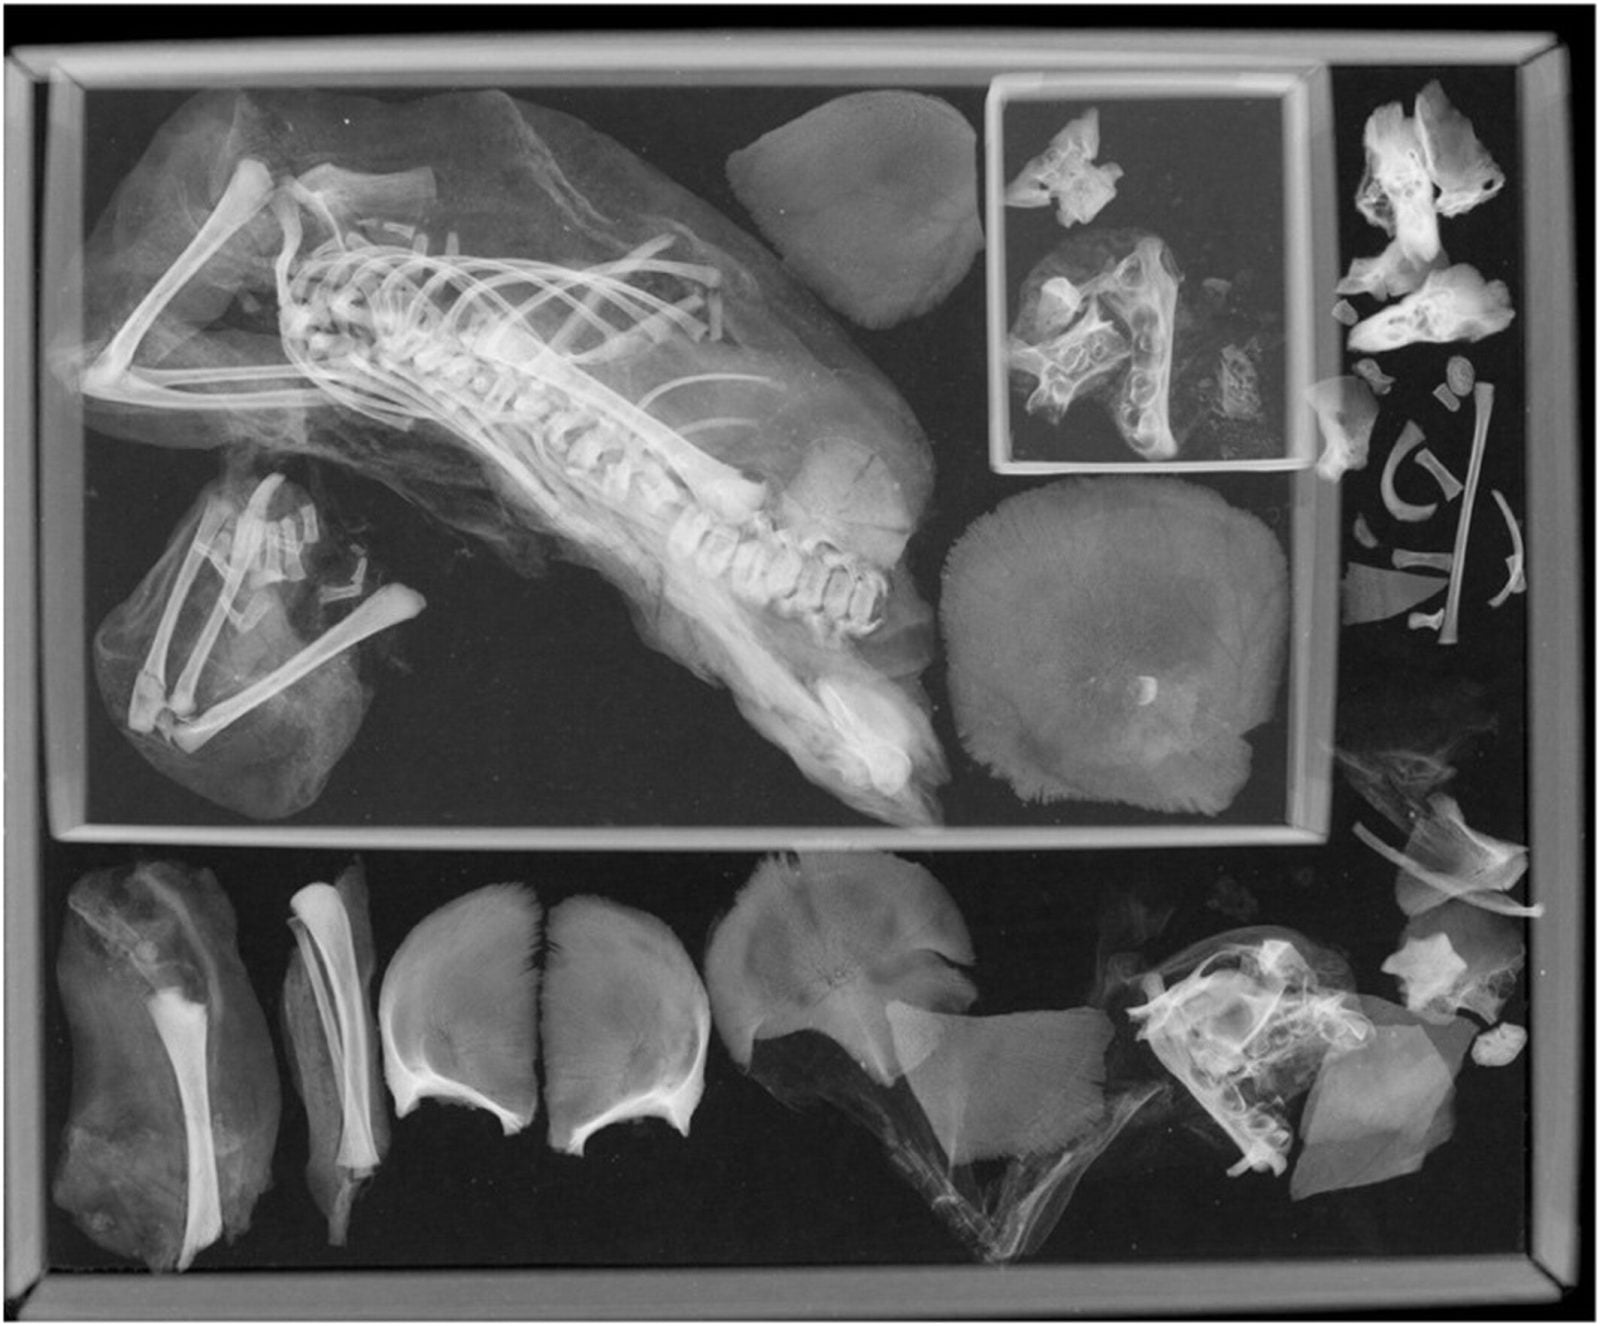

W periodyku International Journal of Osteoarchaelogy pojawiła się niedawno praca naukowa dwójki amerykańskich archeologów, Francine Margolis i Davida R. Hunta, którzy postanowili ponownie przebadać szczątki mumii. Wykorzystali przy tym technikę tomografii komputerowej (CT), aby ustalić, co takiego podczas porodu mogło się wydarzyć, że zmumifikowano kobietę w dość nietypowej pozycji.

Zaskoczeniom naukowców nie było końca – możemy się tak domyślać po tym, co za chwilę przeczytamy. CT wykazało o wiele więcej informacji, niż pobieżne analizy z początku XX wieku. Przede wszystkim nastoletnia kobieta spodziewała się nie jednego dziecka, a bliźniaków. Głowę pierwszego z nich odkryto w miednicy kobiety, a ciało drugiego zlokalizowano w klatce piersiowej. Jak do tego doszło?

Uczeni nie wykluczają, że podczas porodu doszło do dekapitacji (oderwania główki dziecka). Scenariusz ten wydaje się bardzo możliwy, ponieważ w zmumifikowanym ciele kobiety zlokalizowano w okolicach miednicy główkę zmarłego płodu. Reszta ciała wraz z łożyskiem znajdowała się zabalsamowana pomiędzy nogami matki. Nie wiadomo tylko, czy do oderwania główki doszło przypadkowo czy celowo.

Poród pośladkowy wraz z dekapitacją noworodka musiał spowodować śmierć kobiety. Osoby towarzyszące wówczas podczas porodu nie miały zapewne pojęcia, że w ciele nastolatki czekało jeszcze drugie z bliźniąt. Stwierdzono to na podstawie tego, że ciało tego dziecka nie zostało wydobyte ze zwłok matki. Naukowcy natrafili na szczątki bliźniaka dokładnie w klatce piersiowej. Przesunęły się one tam samoistnie, kiedy w drodze rozkładu ciała przepona uległa rozpuszczeniu.

Autorzy badań uciekają od pewnych i finalnych stwierdzeń na temat historii, która wydarzyła się w starożytnym Egipcie ponad 2000 lat temu. Ponowna analiza mumii obejmowała jedynie tomografię komputerową oraz rewizję notatek z 1908 roku. Uczeni wskazują, że potrzebna jest chociażby szczegółowa analiza samych szczątków (częściowo) narodzonego płodu. Póki co potwierdzono, że bliźnięta w momencie śmierci były w 36-40 tygodniu życia płodowego.